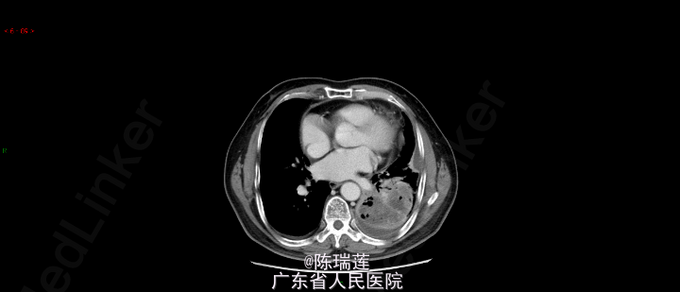

因"反复咳嗽、咳痰1年余,加重1月余" 患者1年余前无明显诱因出现咳嗽,以夜间平卧时为主,偶有咳痰,为白色泡沫痰,无气促,无盗汗、发热,无痰中带血,无大量脓臭痰,无胸闷、胸痛,遂到当地医院就诊,查胸部CT示:左下肺野重叠区巨大团块影(85mm*68mm),性质待定;予止咳、化痰等对症治疗(具体不详)后稍有好转,但上述症状反复发作,外院多次以“支气管炎”或“大叶性肺炎”予抗感染、止咳化痰等治疗(具体治疗不详),效果不明显。1月余前无明显诱因上述症状较前加重,出现痰中带血,、予以止咳、化痰及平喘治疗,症状无明显好转。今为进一步诊治入住我科,患者患病以来精神、睡眠、饮食可,二便正常,体重无明显减轻。 大量吸烟史40余年,40-60支/天,已戒12年

查体:左下肺呼吸音减弱,双侧未闻及干湿啰音。全身浅表淋巴结触及肿大。心律齐,各瓣膜区未闻及杂音。腹部软,无压痛及反跳痛。 查胸部CT示:左肺下叶巨大分叶软组织肿块(78mm*74mm*98mm),注意周围型肺癌可能,肺气肿。

诊断:左下肺鳞癌 行支气管镜检查并活检,活检后病理提示:鳞癌。 因患者住院期间出现发热,予抗感染并止血、止痛、解痉、化痰对症治疗。感染控制后,择期行化疗。